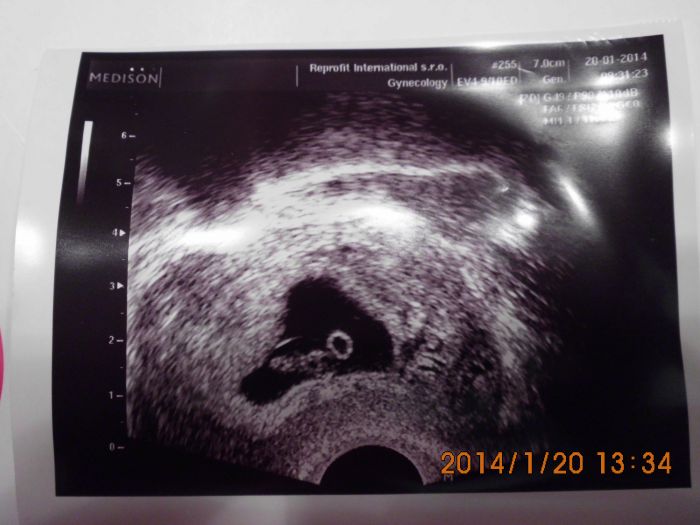

Jinak do přílohy dávám našeho koblížka